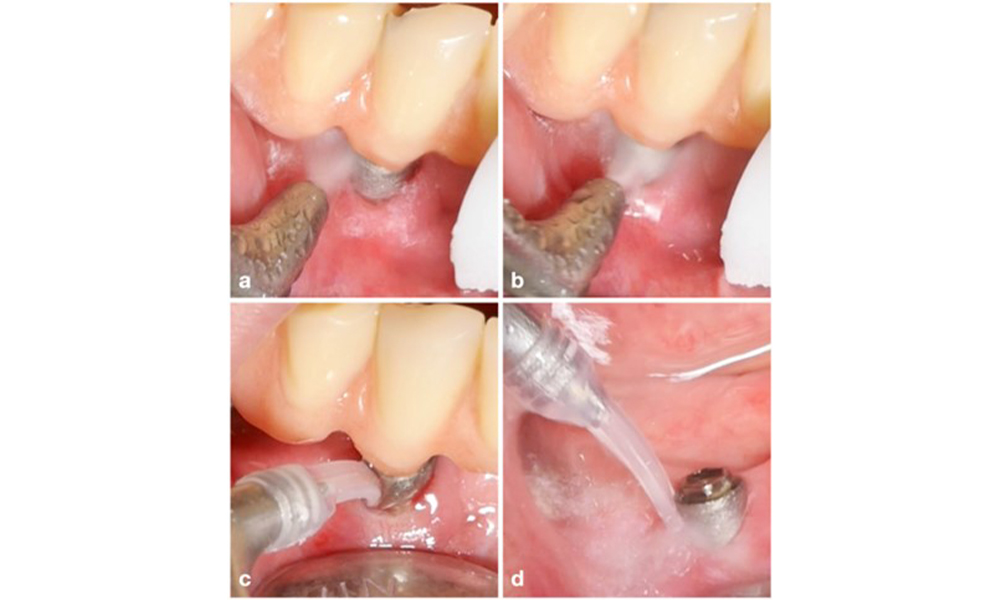

The choice of equipment depends on clinical circumstances, such as the distinction between calculus and soft plaque. Thus, in cases with calculus, titanium or plastic curettes, or specially designed tips for ultrasonic scalers should be used first, followed by the use of an air-polishing device (figure 7). In cases with only soft plaque accumulation, an air-polishing device alone can be sufficient. Air-polishing devices are operator and patient friendly and at least as efficient as standard instruments (Schwarz et al. 2015a).

Patient case with peri-implant mucositis, poor oral hygiene and calculus accumulation (a). In such case the combination of different equipment is advisable, i.e., specially designed tips for ultrasonic scalers are necessary to remove the calculus (b), and an air-polishing device helps in removing remaining soft biofilm (c–d).